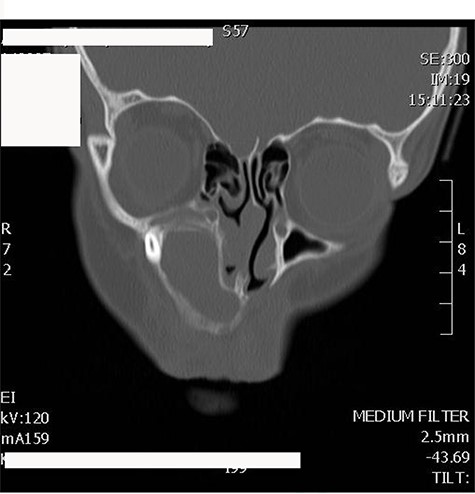

A 13-years-old boy medically and surgically free presented to the otolaryngology clinic with swelling of the right side of the face for 1 month, no other significant symptoms. Patient has history of facial trauma 8 years back. Examination was unremarkable apart from right-sided facial swelling over the maxillary sinus. Computed tomography (CT) of the paranasal sinuses showed a large expansible cystic lesion in the right maxillary bone that arises from the maxillary alveolar ridge with superior extension and displacement of the right maxillary sinus. A displaced tooth is seen within the anterior aspect with its root pointing posteriorly to the floor of the hypoplastic maxillary sinus with its crown embedded within the lesion (Fig. 1).

CT scan of maxillofacial bones showing a large expansible cystic lesion in the right maxillary bone that arises from the maxillary alveolar ridge with superior extension and displacement of the right maxillary sinus as well as remodeling of the floor of the right orbit with slight narrowing of the right inferior orbital fissure.